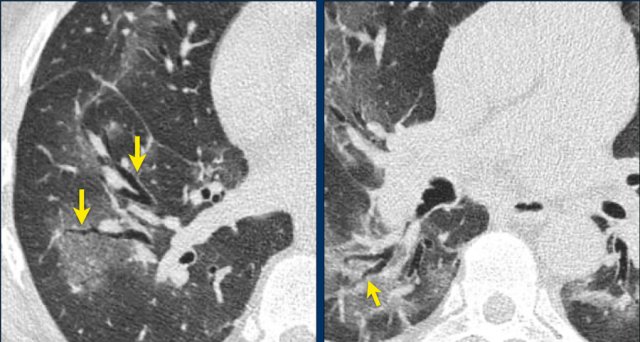

A typical finding in the area of ground glass is widening of the vessels (arrow).

Another common finding in the areas of ground glass is traction bronchiectasis (arrows).